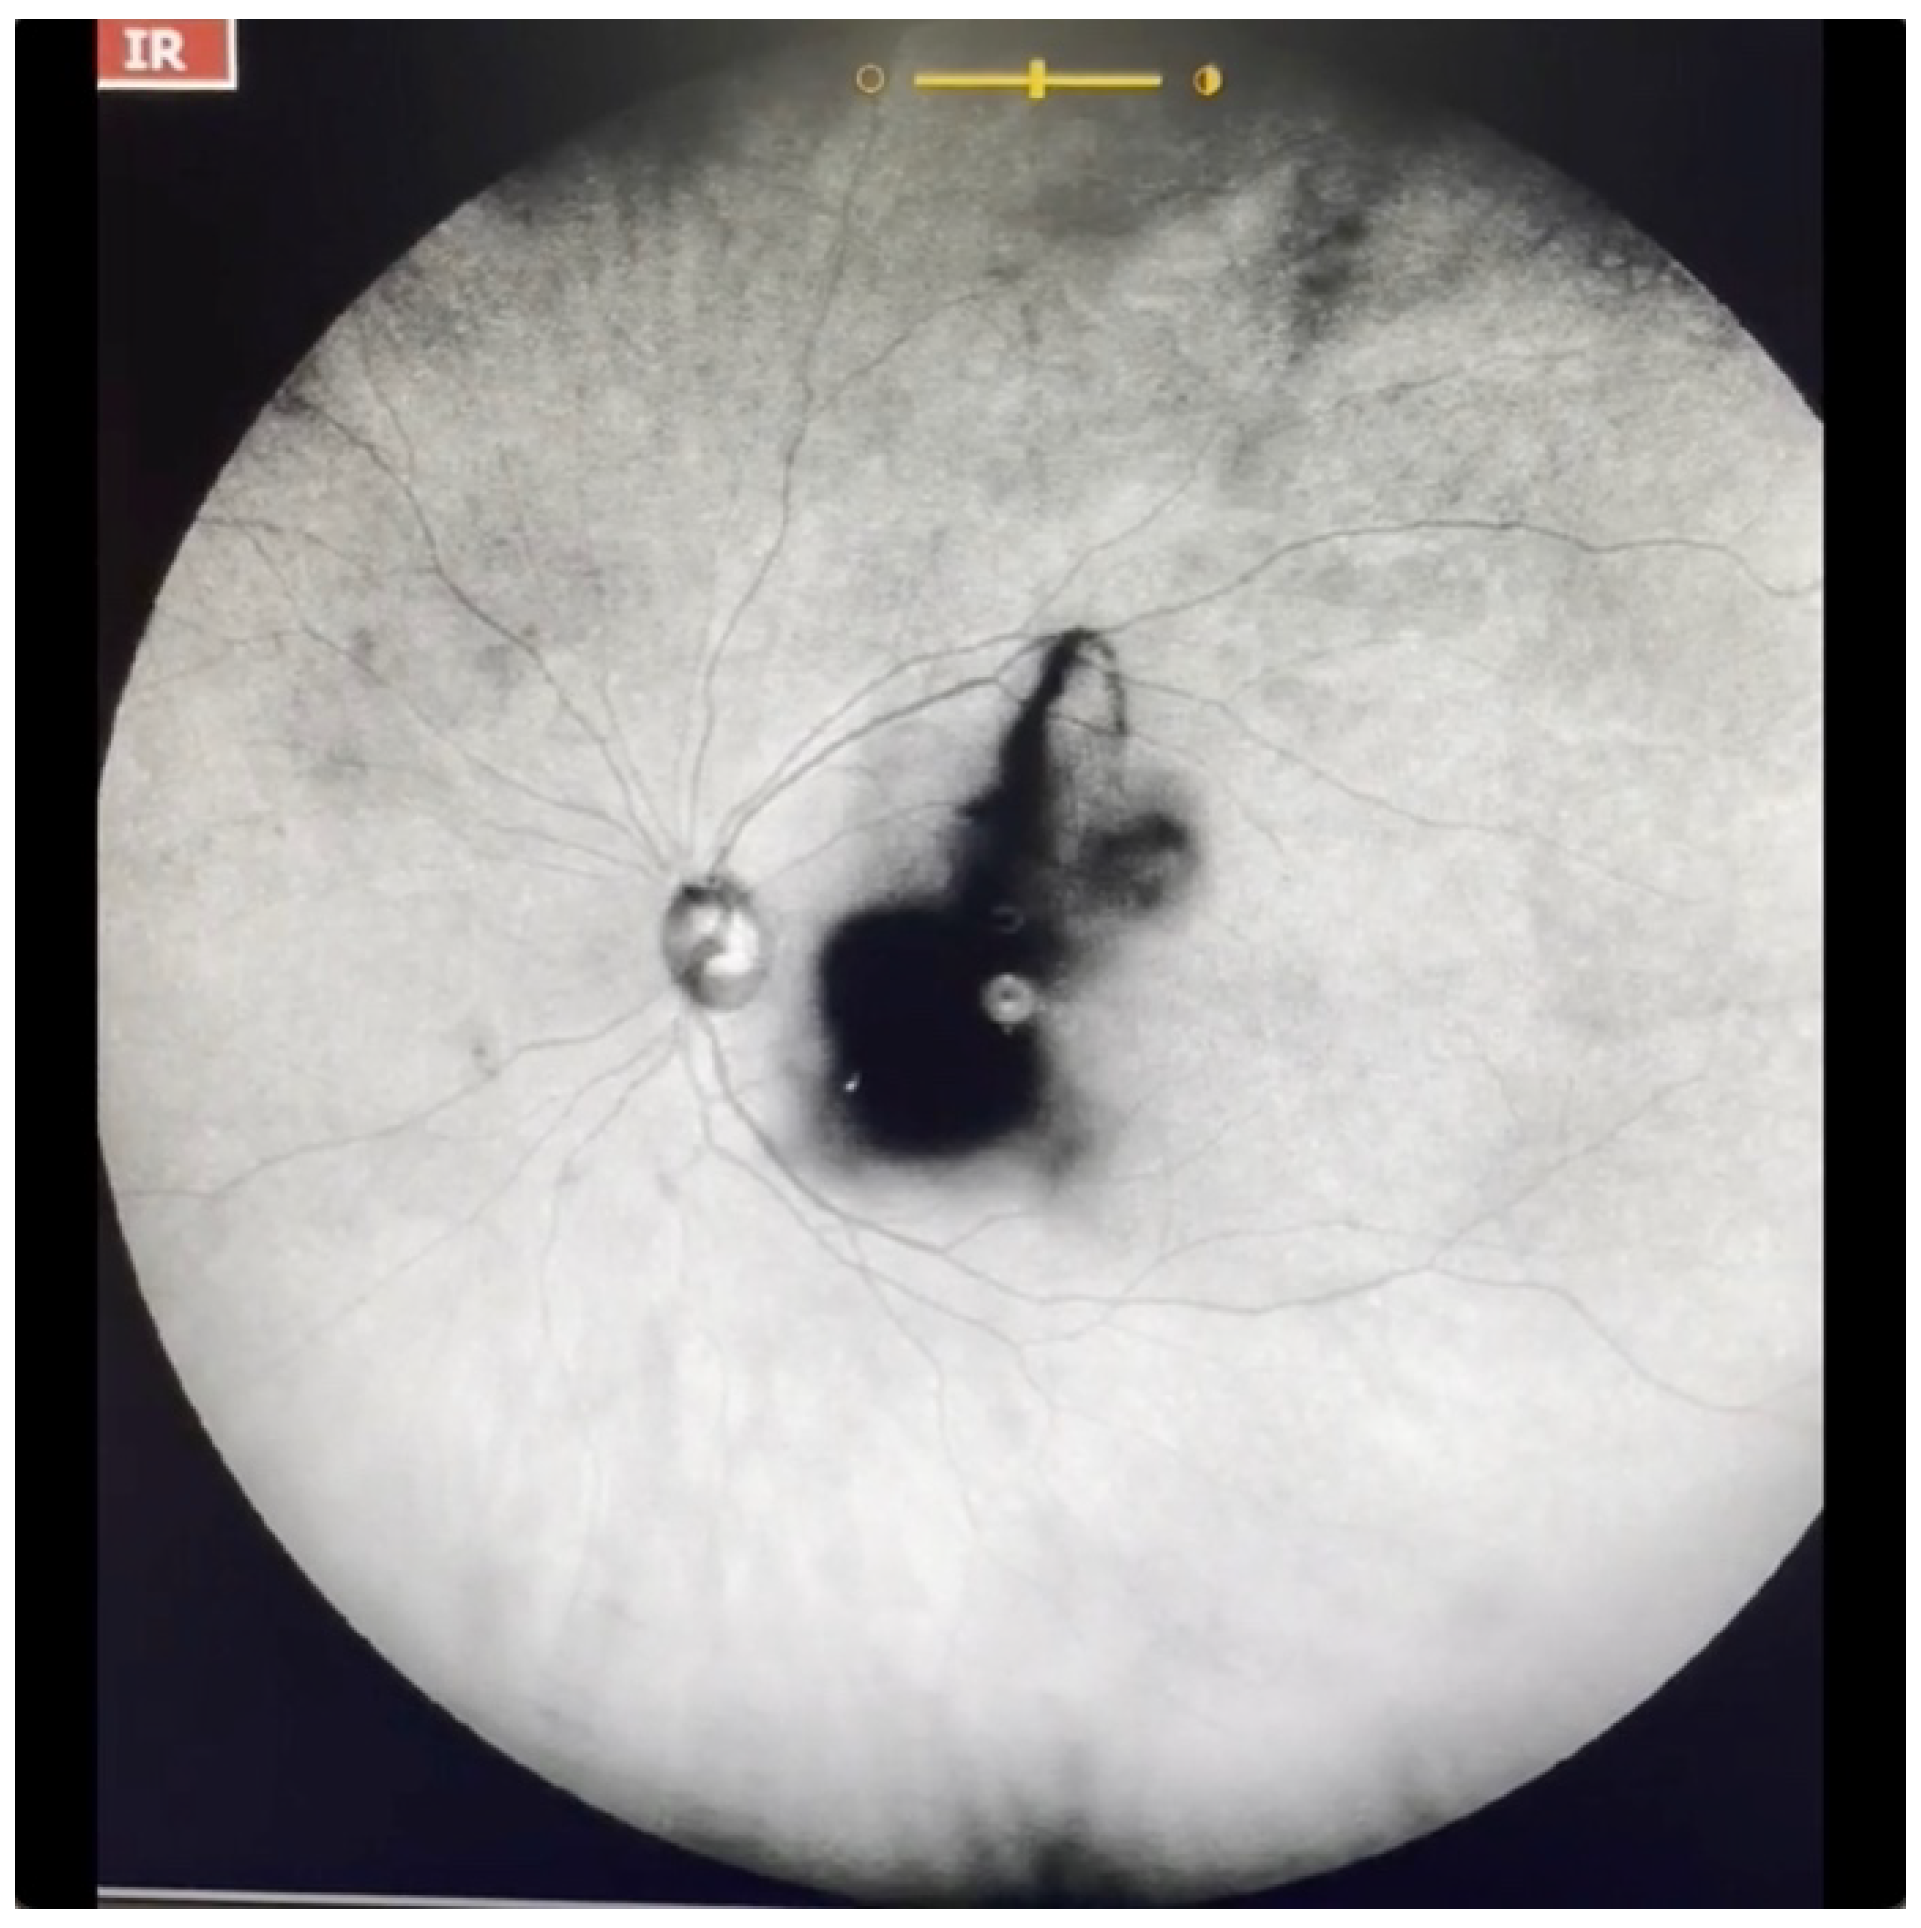

| Grade 5—Dense opacities that obstruct at least 30% of the macula (~2 disc diameters in size) (Figure 7 and Video S7). |